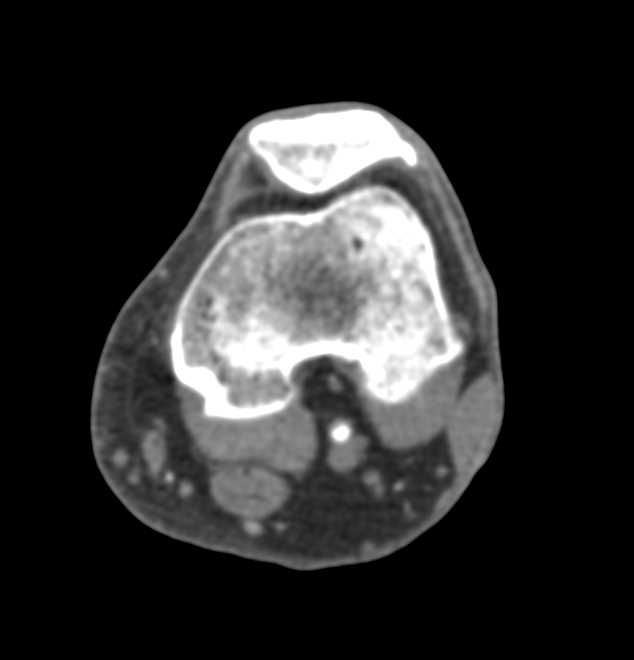

CTA with Plaque in the Popliteal Artery on Runoff Study